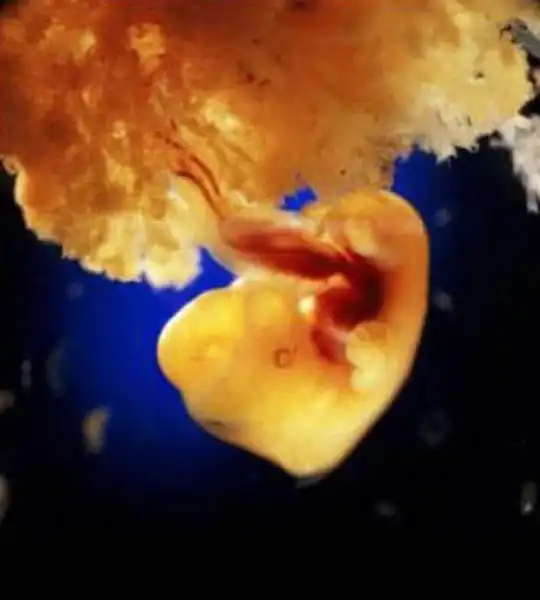

Через неделю зародыш, скользя вниз по фаллопиевой трубе, переселяется в матку...

Эмбрион, прикрепленный к слизистой матки (+8 дней)

40 дней. Наружные клетки зародыша срослись с рыхлой поверхностью матки и образуют плаценту, или детское место. Это губчатый кусок плоти служит человеку в первые девять месяцев его жизни и легкими, и желудком, и печенью, и почкой...